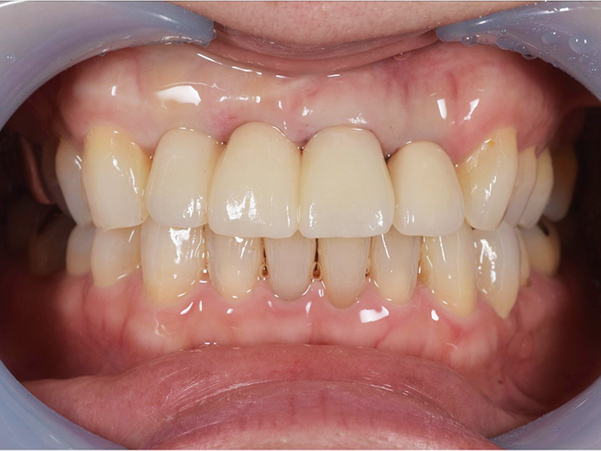

上部構造物装着

上部構造物を装着した状態です。まだ装着して日が浅いので、今後歯ぐきとの馴染みが十分ではありません。

インプラントは虫歯にはなりませんが、インプラント周囲炎になる可能性がありますので、今後は定期検診で確認し、健康な状態を維持していくよう努めていきます。